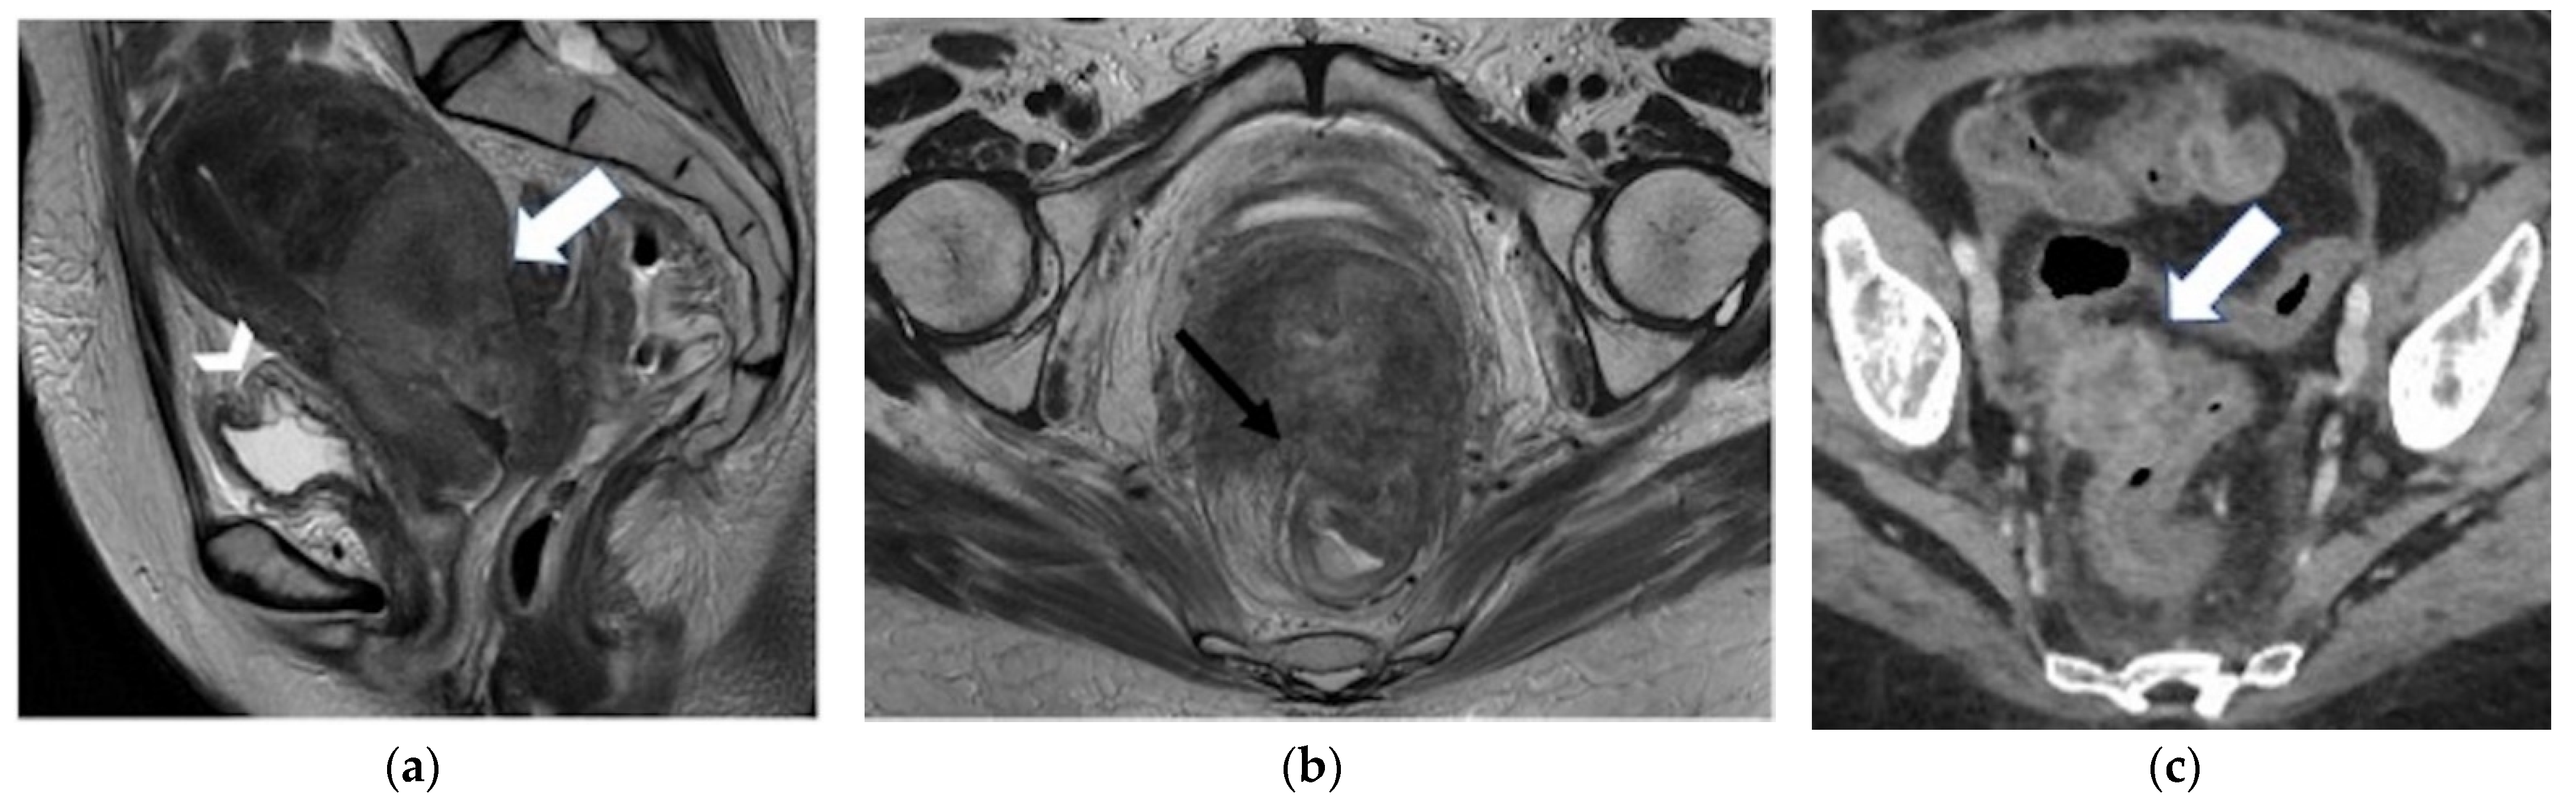

| Lateral Pelvic sidewall ![]() | Pelvic sidewall recurrence is defined as a tumor extending within 3 mm and abutting the obturator internus or piriformis muscles with concomitant loss of fat planes. Other findings include:

|